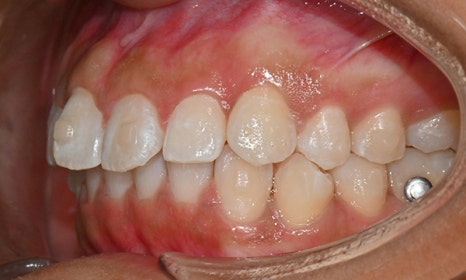

교정 마무리 후 사진 (2025.8)

교정 마무리 후 사진으로 위아래 치아 배열이 개선되었고 공간이 모두 닫혔습니다. 위아래 앞니가 깊게 물리는 과개교합도 처음에 비하여 많이 개선되었습니다. 다만 아래 작은 어금니 배열로 인하여 왼쪽 어금니 교합은 아직 완벽하지 않은 상태로, 추후 본국으로 돌아가서 자료를 transfer 해드려서 이어서 치료를 받기로 하셨습니다.

위 오른쪽 앞니의 경우 초진시에도 틀어져있던 부위의 잇몸이 내려가 있었으므로, 치아가 배열되면 좌우 잇몸 높이가 맞지 않을 것임을 미리 고지시켜드렸었고, 추후 치은성형술로 잇몸 높이를 맞추는 것이 심미적으로 더 보기 좋을 것임을 추천드렸습니다.

약 4개월의 기간 동안 처음부터 마무리까지 총 5번의 내원으로 교정치료가 마무리 되었으며, 위아래 앞니 고정식 유지장치 및 Vivera 유지장치를 착용 후 출국하셨습니다.